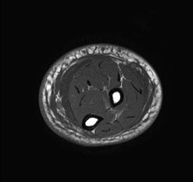

- Thigh MRI

Ideal examination for studying injuries to the hamstrings and quadriceps, which are frequently injured in athletes. It also allows for a good assessment of tendons and peripheral nerves. It lasts approximately 20 minutes. It is a radiation-free procedure.

- Leg MRI

Examination to study injuries to tendons, muscles and peripheral nerves. Very useful for diagnosing fibrillar tears in twins. It lasts approximately 18 minutes. It is a radiation-free procedure.